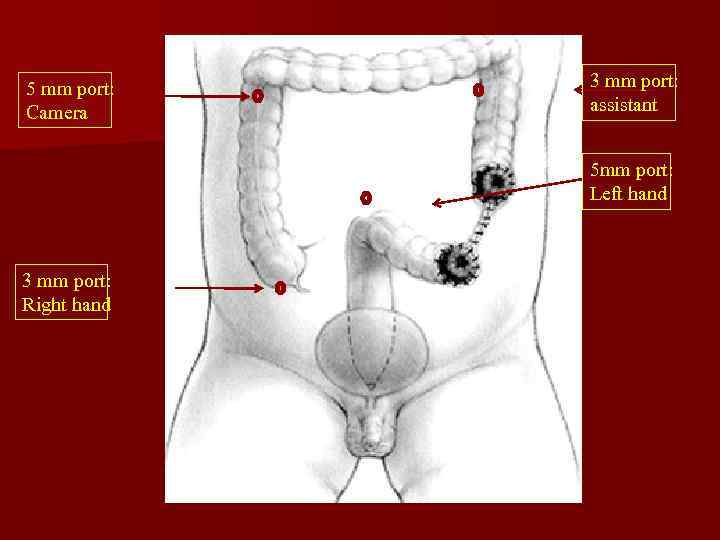

На абдоминальном этапе операции возможна лапаротомия или лапароскопия

Этапы операции…

5 mm port: Camera 3 mm port: assistant 5 mm port: Left hand 3 mm port: Right hand